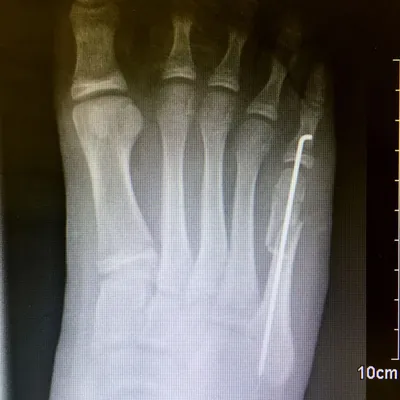

Pediatric Displaced 5th Met Distal shaft/neck fracture

Preop Pics of the displaced fracture prior to Percutaneous Fixation and Reduction

We percutaneously put a pin across the fracture after closed reduction for 12-16 weeks. The last picture is a final after the fracture is healed and the pin is removed.